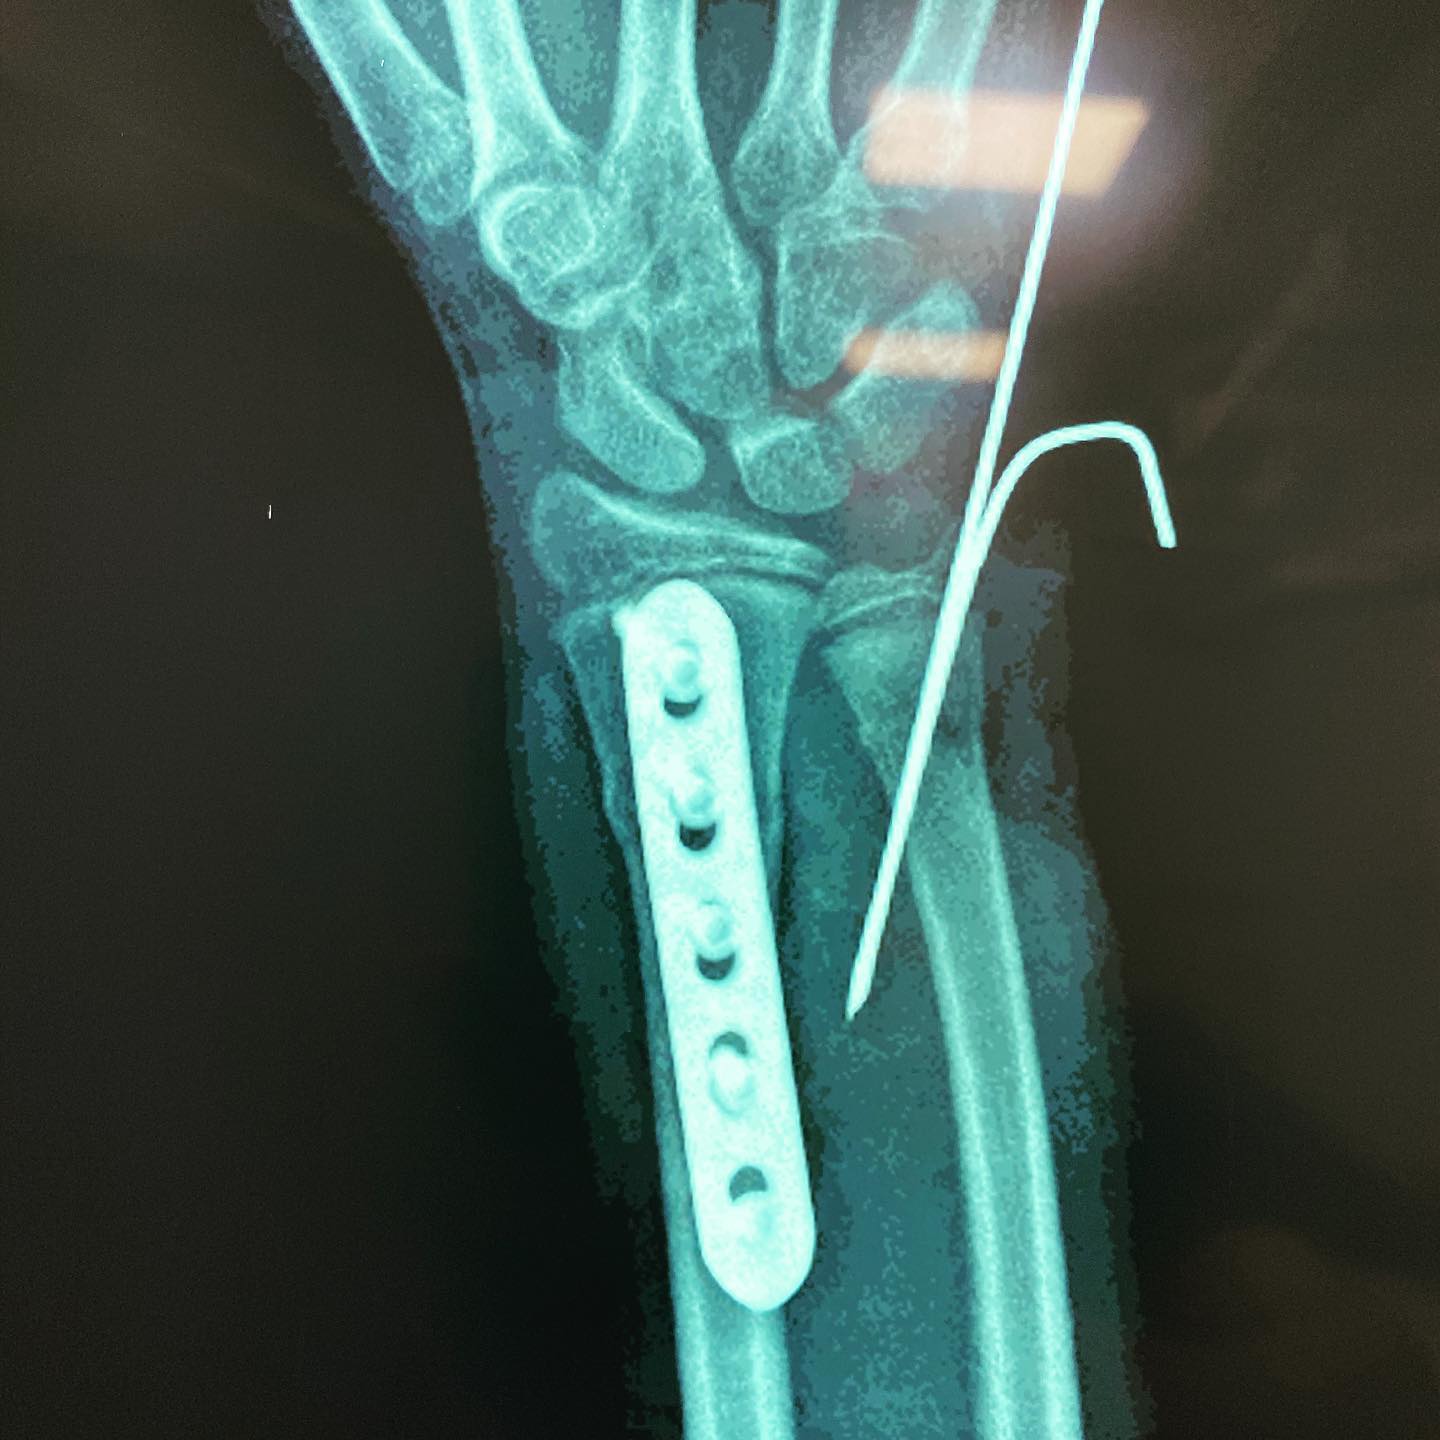

fractura de antebrazo

Cité a Josué para seguimiento y como ya está recuperado al 💯 de la cirugía por fractura de su antebrazo, le di el alta. En su visita me regaló una deliciosa sandía.🍉